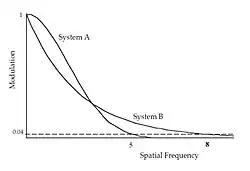

Spatial frequency, B, in Figure 6.9 can be considered to be approaching the extreme of the resolving capability of an imaging system. The limiting spatial resolution is sometimes defined as the frequency where the modulation drops to 4%. When the resolving ability of two different image receptors is compared, as in Figure 6.10 for instance, we could infer from measuring the limiting resolution alone that system B was superior to system A, at 8 compared to 5 LP/mm. An MTF comparison would reveal however that system A in fact provides superior quality at frequencies less than about 3 LP/mm, which is where many features of clinical interest said to lie.